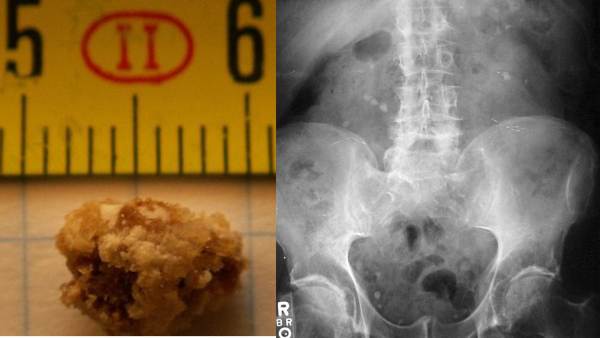

Dietary Guidelines For Managing Kidney Stones

Kidney stones are a painful experience to go through, they are the deposits of hard solids and minerals that get accumulated in the kidney causing pain. Kidney stones develop when urine crystallises and sticks together.